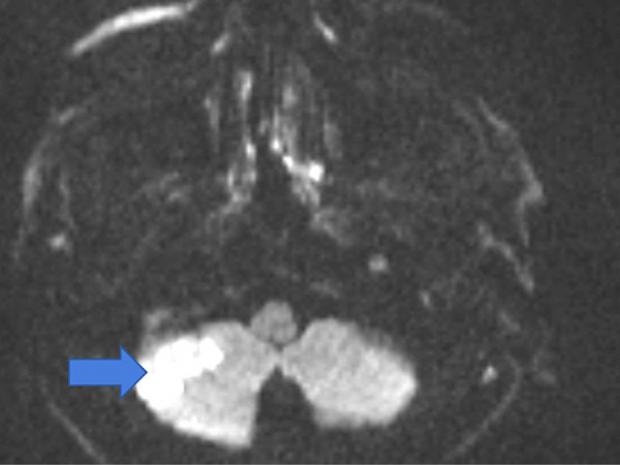

وأوضح الدكتور مايكل وينتراوب، إن السكتة الدماغية تحدث عندما ينقطع تدفق الدم إلى الدماغ، غالبًا بسبب جلطة أو تمزق الأوعية الدموية، فعندما يؤثر وضع الرقبة أثناء غسل الشعر في الصالون على تدفق الدم، قد يؤدي إلى مضاعفات خطيرة.

وضعية الرقبة السبب الحقيقي للأزمة، فعندما تتكئين على حوض المغسلة، تكون رقبتك ممدودة وأحيانا تهتز أثناء غسل الشعر، ووفقًا لصاحب الدراسة، يمكن أن يتسبب ذلك في ضغط أو تلف الأوعية الدموية المؤدية إلى الدماغ، أو حدوث بعض الأعراض مثل نتوءات العظام أو إصابات الرقبة أو مشكلات الأوعية الدموية، وقد يؤدي هذا الوضع إلى حدوث سكتة دماغية.